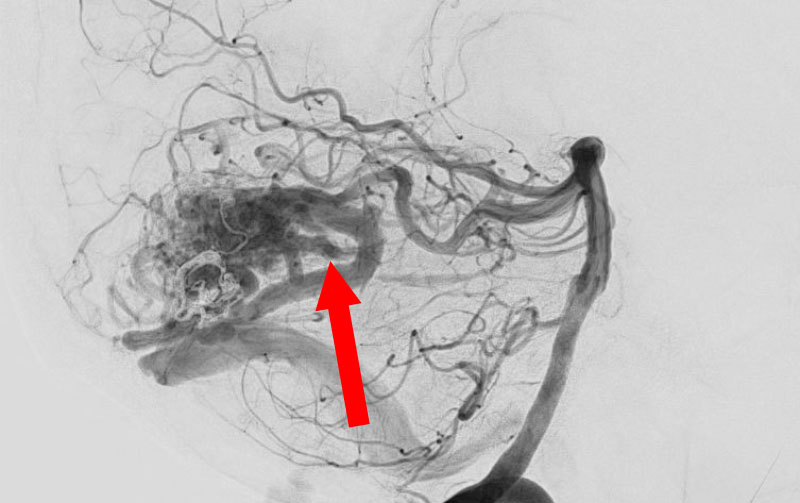

No.1596 手術前